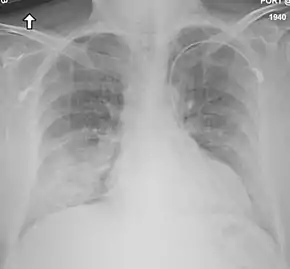

Medical imaging

Chest X-ray findings tend to show bilateral patchy infiltrates consistent with viral pneumonitis and acute respiratory distress syndrome (ARDS). Lower lobes tend to be more involved. CT scans show interstitial infiltrates.[24]